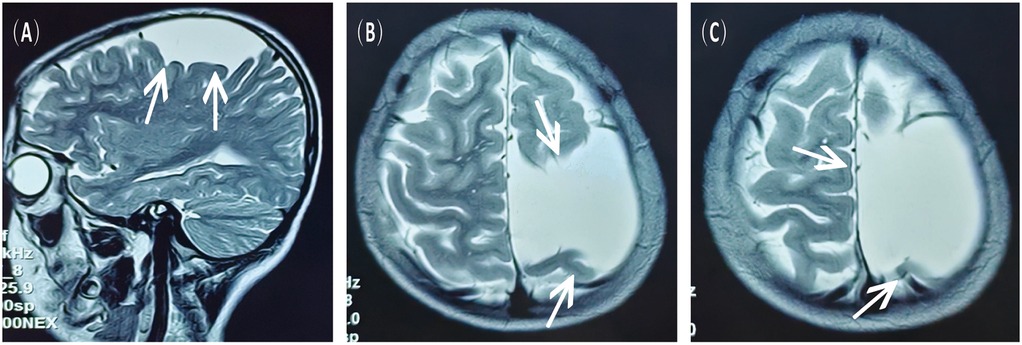

A 16-year-old male presented to the hospital with a 10-day history of episodic headache. Three years earlier, he had been evaluated for headache, and magnetic resonance imaging (MRI) identified an arachnoid cyst in the left fronto-temporo-parietal region (Figure 1). Given the absence of significant mass effect or neurological deficits and the resolution of symptoms, surgical intervention was not advised at that time. No specific intervention was performed, and the headache subsequently resolved on its own. No further imaging studies were conducted thereafter. Ten days ago, the patient experienced recurrent headaches without apparent cause or trigger, characterized by episodic attacks predominantly localized to the left occipital region. The headache was initially relieved by oral painkillers but reappeared 2 days before admission to the hospital, worsening compared to the previous episode. For further evaluation and management, the patient presented to our institution. An outpatient magnetic resonance imaging (MRI) revealed a massive chronic subdural hematoma (CSDH) in the left fronto-temporo-parietal region (Figure 2). No computed tomography angiography (CTA) or digital subtraction angiography (DSA) was performed at this time. The patient underwent burr-hole irrigation and drainage of the CSDH under general anaesthesia. Concurrently, the cyst wall was fenestrated to establish communication between the cyst and the extracerebral space. Postoperative imaging confirmed complete resolution of the hematoma and a significant reduction in the size of the cyst (Figures 3A–C). His headaches were relieved significantly compared with those of the previous day. The cyst did not recur on the patient's return visit 6 months after the operation (Figures 3D–F), and no symptoms such as headache were observed during the 6 months.

Figure 1. MRI scans obtained 3 years prior to the current admission, showing the left fronto-temporo-parietal arachnoid cyst. (A) Sagittal view, T2-weighted sequence. (B,C) Axial view, T2-weighted sequence.